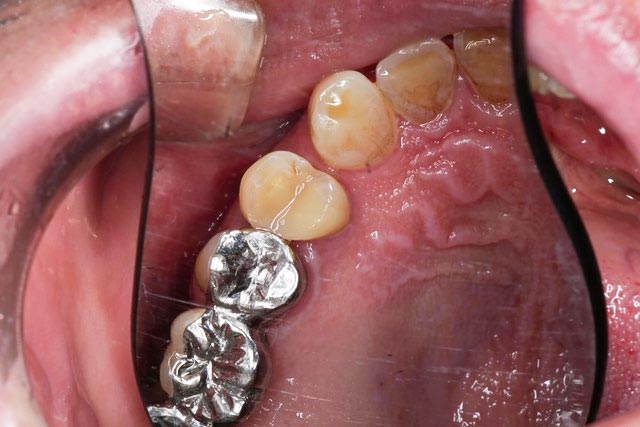

むし歯を除去した後は歯を作っていきます。

歯をしっかり処理をして、歯の内部の色、表面の色、透明感を与える色の修復材料を直接接着させていきます。

鈴木歯科医院ではセラミックスを特殊なセメントで接着させる方法と、今回のように直接修復するダイレクトボンディングを推奨しています。

どこを治したかわかりますか?銀歯の隣の歯です。

歯の神経を残すということは、今後の歯の予後を良好な結果に保つことにつながります。